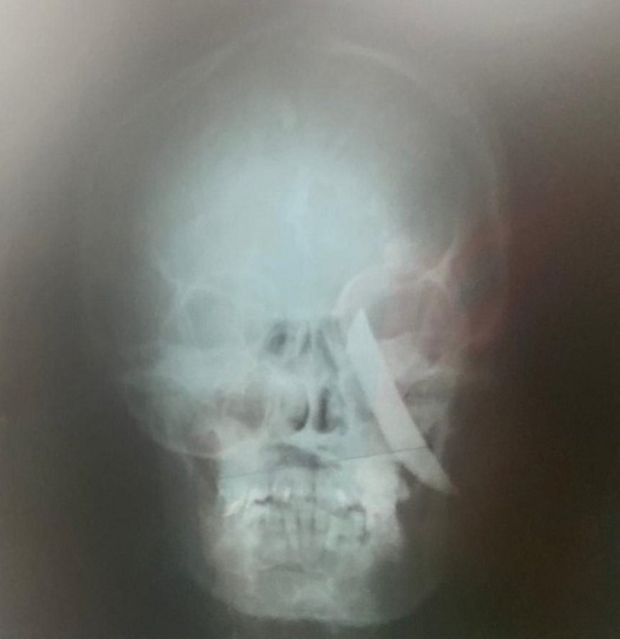

Na madrugada deste domingo (26/9), um adolescente de 17 anos e um homem de 24 anos foram feridos com golpes de faca em Samambaia. O menor de idade, segundo o Corpo de Bombeiros Militar do Distrito Federal (CBMDF), foi encontrado com uma faca cravada na parte temporal do crânio, do lado esquerdo, próximo do globo ocular. Ele foi transportado ao Hospital de Base consciente e estável.

O menor de idade, segundo o Corpo de Bombeiros Militar do Distrito Federal (CBMDF), foi encontrado com uma faca cravada na parte temporal do crânio, do lado esquerdo, próximo do globo ocular. Ele foi transportado ao Hospital de Base consciente e estável.